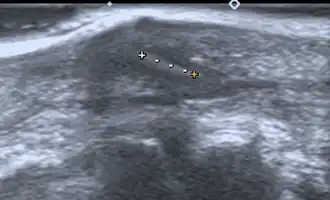

Imaging

If manual detection and localization fail, the main methods for medical imaging of splinters are:

- Medical ultrasonography – used to locate glass, metal, pencil graphite, some plastics, stone, and some types of wood.[6]

Small wooden splinters (1–4 mm) distant from bones are most easily detected by ultrasonography, while CT scan and magnetic resonance imaging have higher sensitivity for those near bones.[7]